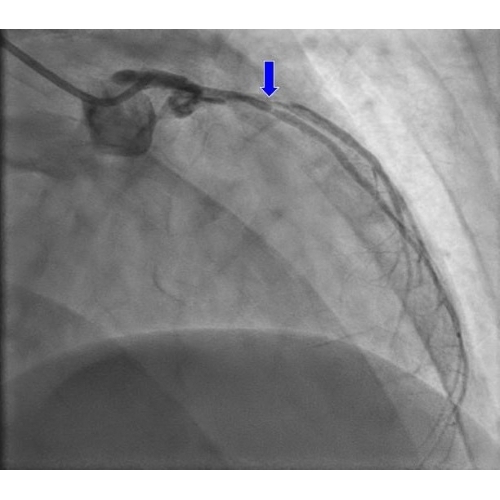

| Syncope In The Athlete - Page #3 | |||